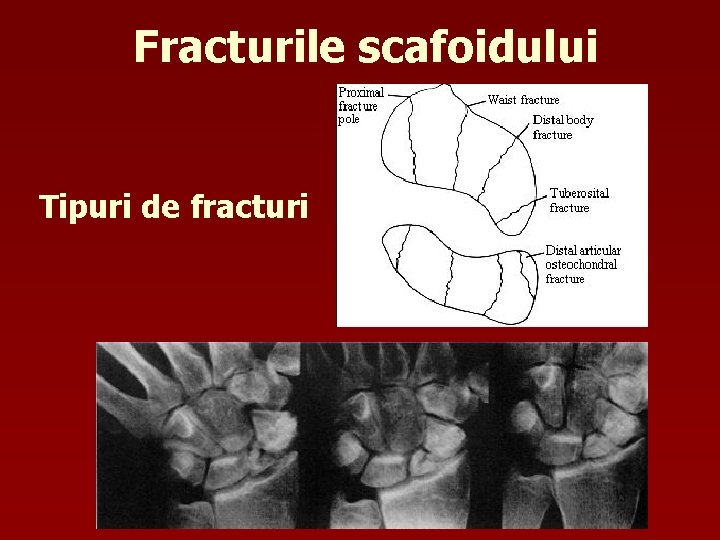

Fracturile scafoidului Tipuri de fracturi